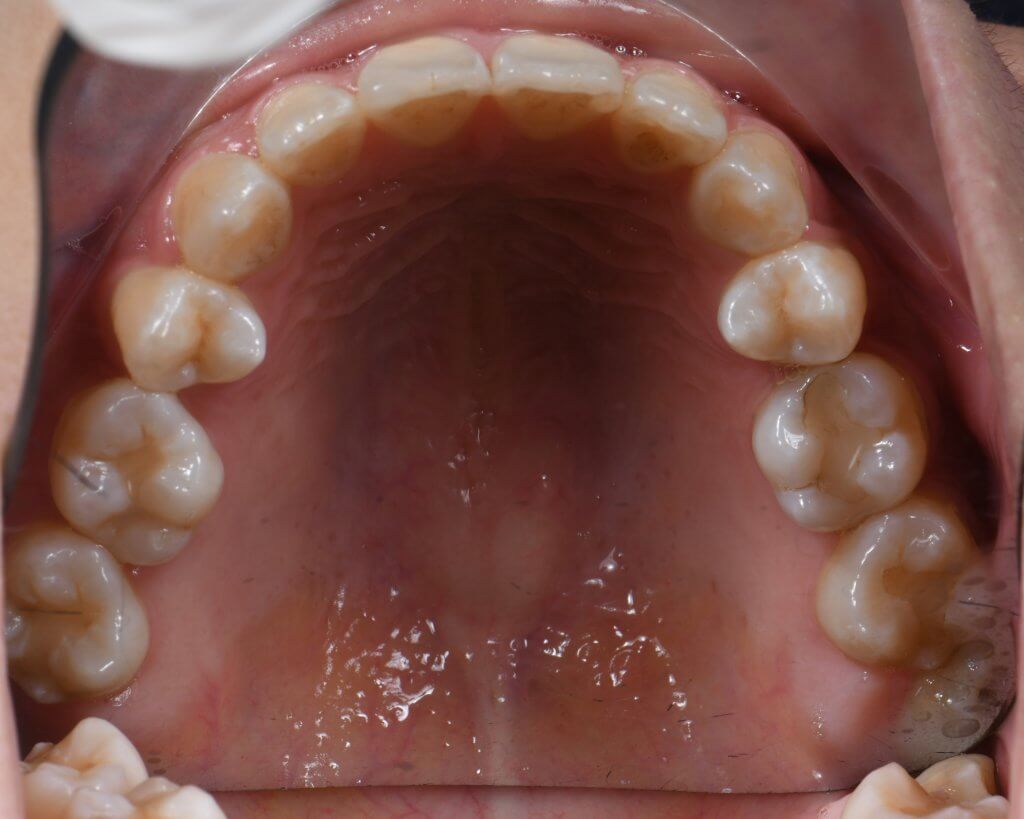

為了騰出足夠的後退空間以改善嘴突,我們決定拔除四顆第一小臼齒。治療核心在於「錨定控制」:

- 上顎後收: 利用後方大臼齒作為錨定點收回前牙,同時配合頭帽(Headgear)提供額外的垂直向力量,除了能有效壓入前牙改善笑齦,更能防止門牙在後退過程中發生過度內傾(Tipping)的問題。

- 下排排齊: 利用拔牙後的空間將擁擠的下齒列重新排列,並同步往後收納。